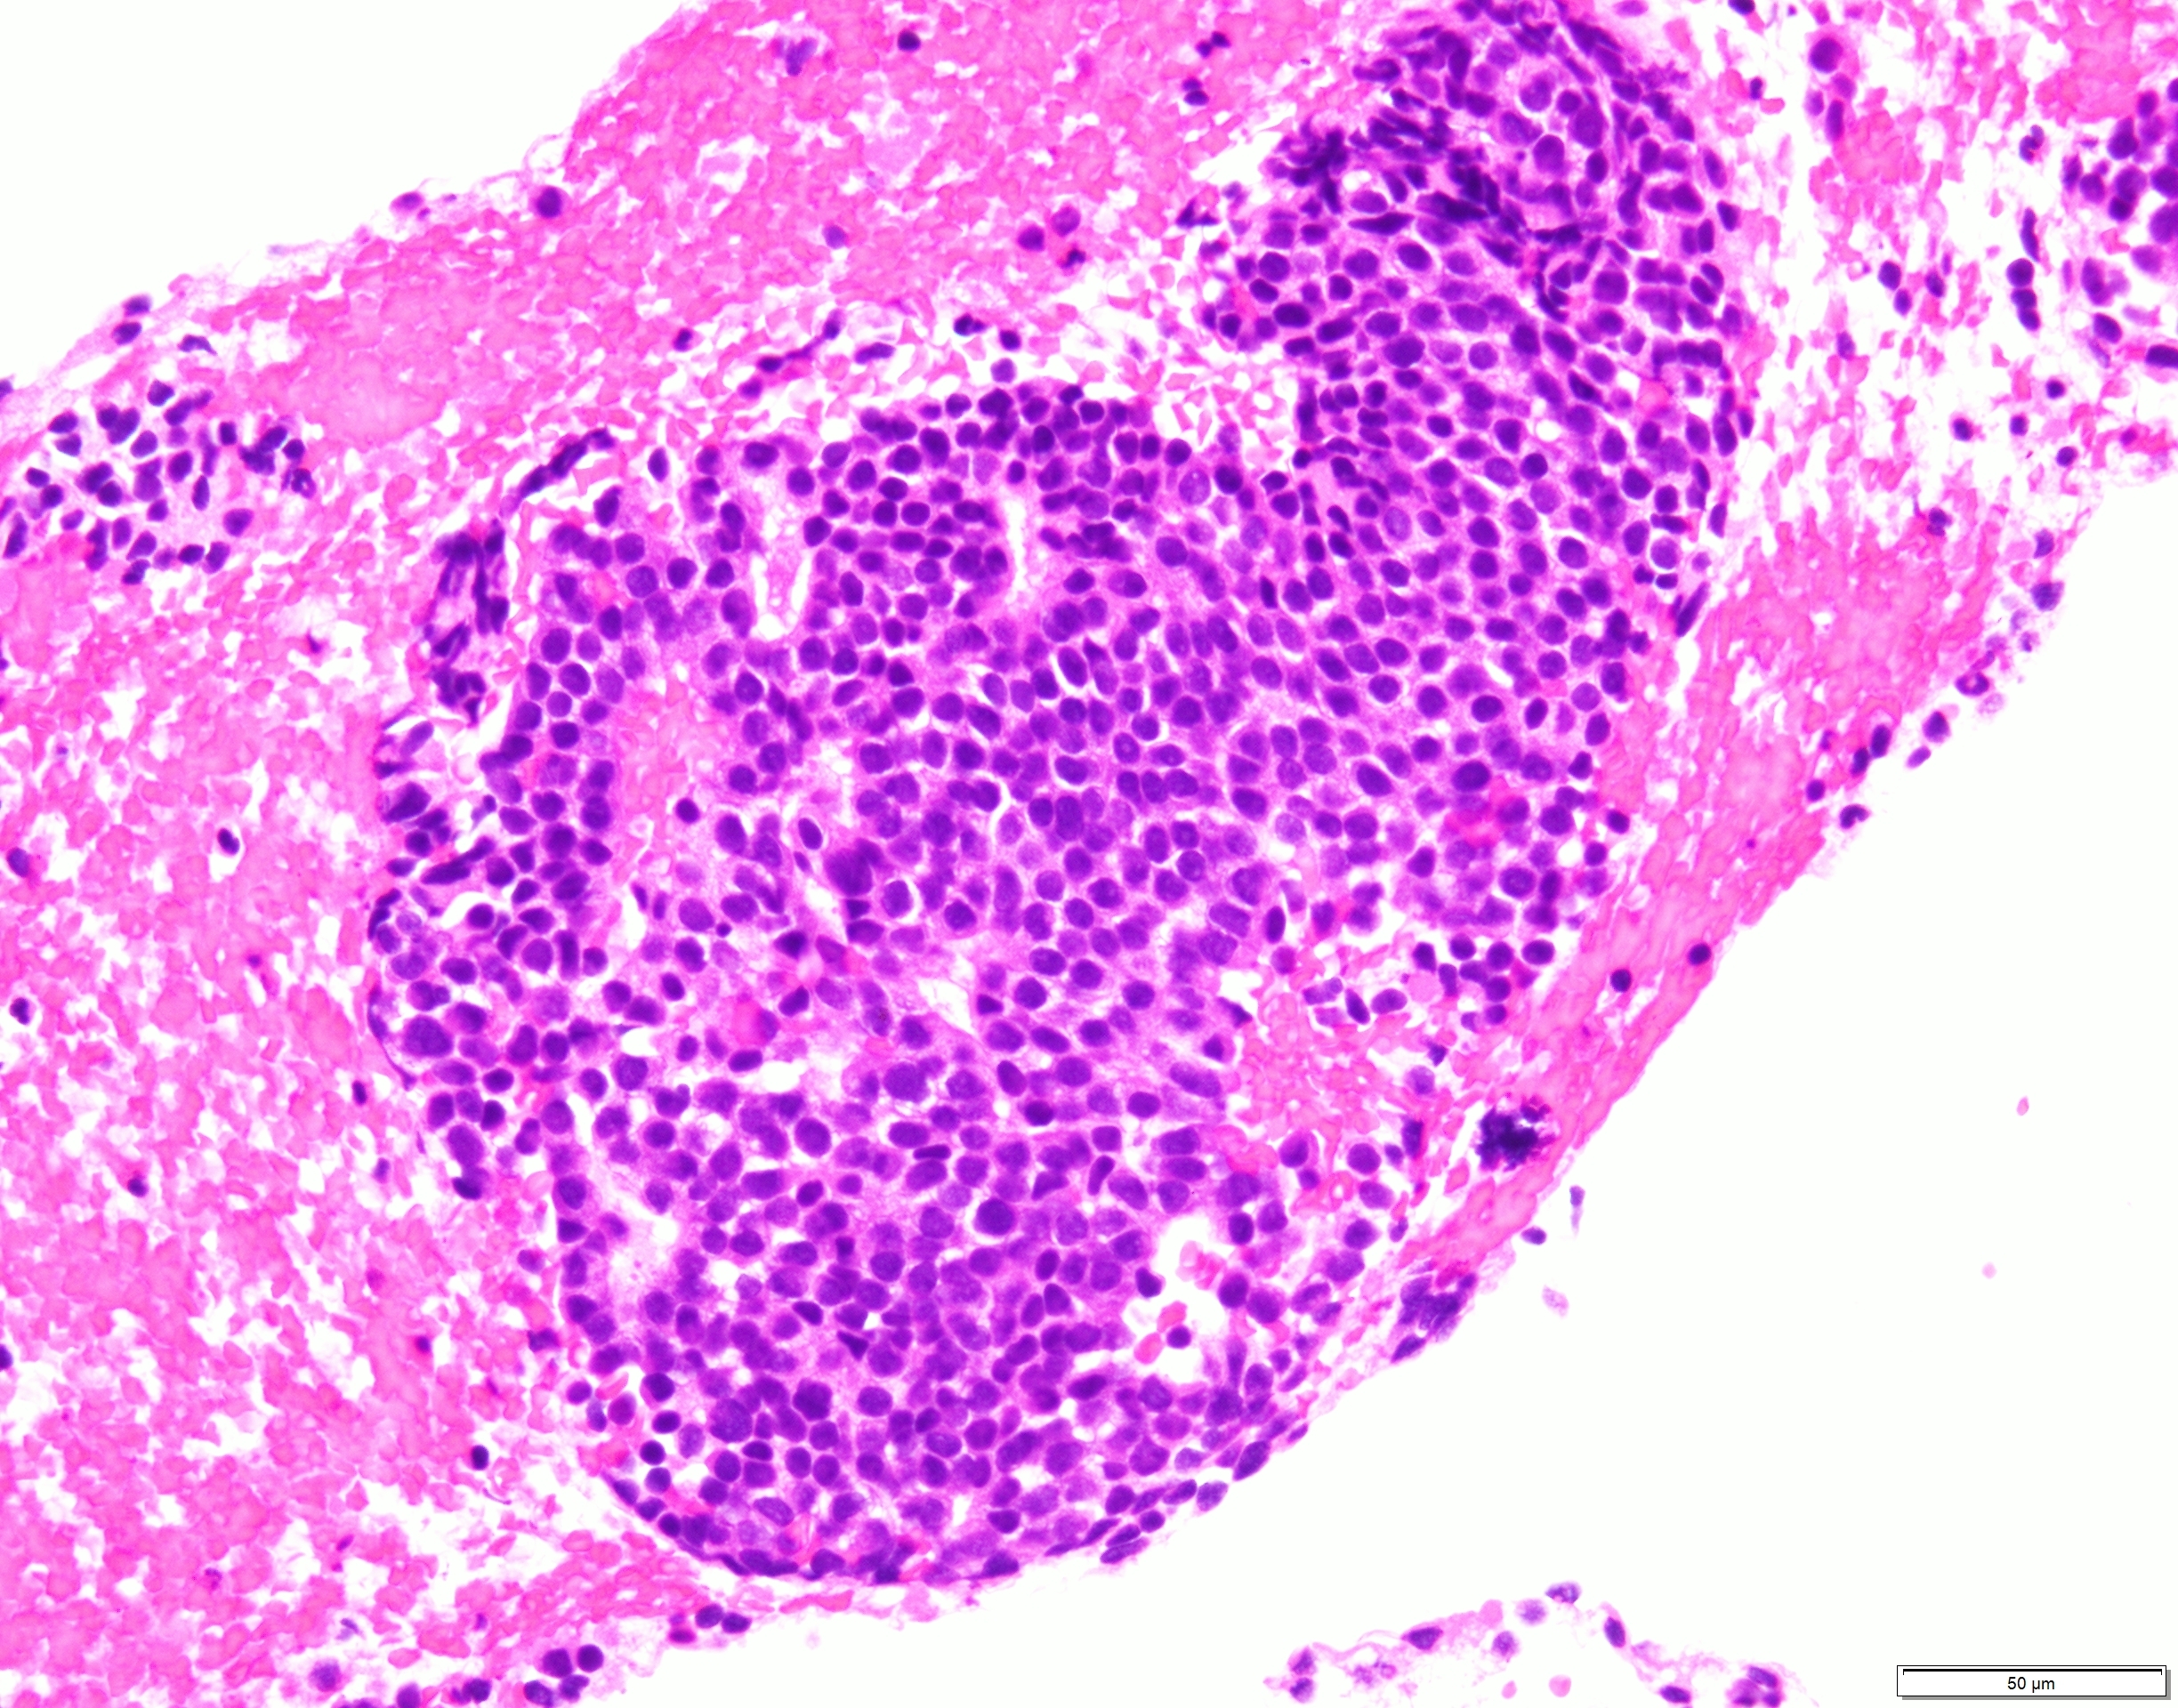

比較的小型で類円形核を有するN/C比の高い細胞が集簇性〜孤立性に多数認められた。

出現している異型細胞は一様で核線の形成やロゼット様の構造を認め、NETを推定した。

異型細胞が血管間質を伴うように出現する箇所も見られ、細胞の形態からもSPNとの鑑別を要する細胞像であるとの意見もあった。

組織でも同様の異型細胞を認め、クロモグラニン陽性、MIB-1 LI 15%、ER陰性、GATA3陰性を呈し、NET G2と診断された。

HE×10 HE×20 HE×40 クロモグラニン×40